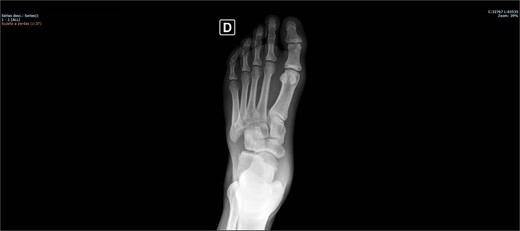

On physical examination, there was pain upon palpation over the dorso-lateral region of the midfoot, mild edema, hyperemia, inability to walk, and restricted ankle extension. Based on the physical examination, radiographs were requested. The examinations (Figs 1 and 2) showed inferomedial displacement of the cuboid bone without the presence of a fracture, diagnosing an isolated cuboid dislocation. He was immobilized and admitted for an open surgical reduction procedure.